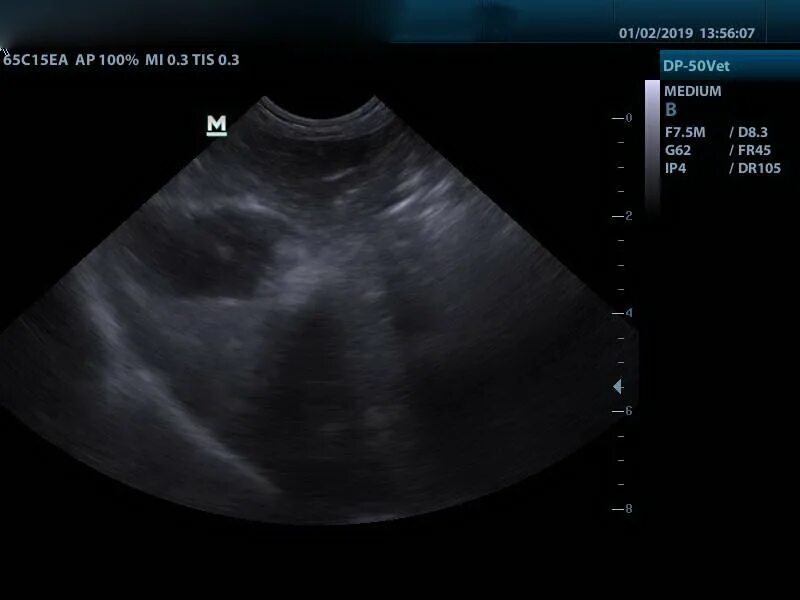

Метастазы в печени на узи прогноз